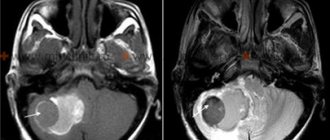

— Which doctor should you contact in this case? What tests are usually ordered?

— Such a child needs to be shown to an epileptologist or neurologist, somnologist, or neuropsychologist. The instrumental examination plan includes electroencephalography; if indicated, an MRI or CT scan of the brain may be performed, especially if sleepwalking has developed after a traumatic brain injury or neuroinfectious disease.